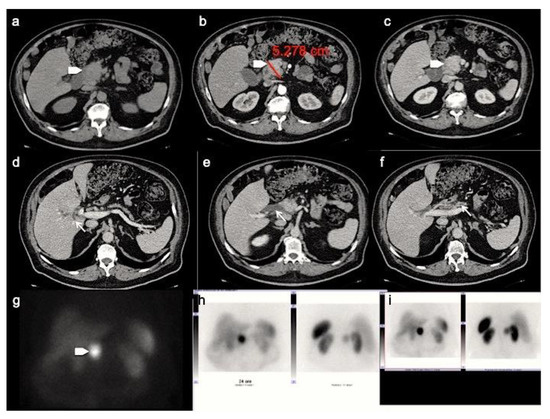

At pre-contrast CT examination, panNENs typically appear as well-rounded, isodense or slightly hypo-dense lesions, with a homogeneous pattern and regular margins [28]. Following the administration of intravenous contrast material, panNENs typically tend to hyper-enhance during arterial phase and demonstrate a slow washout, appearing hyper-dense or isodense among the surrounding parenchyma during portal phase (Figure 1) [29,30]. This typical presentation is more frequently seen in functioning tumors; non-functioning panNENs, especially large ones, more often tend to have an atypical appearance.

Figure 1.

PanNET G1 according to the 2019 WHO classification. CT images in the transverse plane during the basal (a), the arterial (b), the portal venous (c) and the delay (d) phases show a small pancreatic hypervascularized tumor of the pancreatic tail with sharp margin (arrow).

The most common atypical presentations are the hypo-enhancing pattern (Figure 2), the intra-vessels growth, the intra-ductal growth and the cystic and calcified variants, aspects that can make difficult the radiological differential diagnosis with pancreatic ductal adenocarcinoma [31]. Furthermore, as recently demonstrate by Kim. Et al., panNENs with uncommon findings are associated with a significantly worse survival rate [31].

Figure 2.

Patient with liver metastases from poorly differentiated pancreatic neuroendocrine carcinoma. CT images in the transverse plane during the basal (a), the arterial (b) and portal (c) phases show a large mass developed in the pancreatic tail with atypical hypo-enhancing pattern (arrow). This lesion is associated with multiple liver metastases (arrowheads) that appear hypodense with rim enhancement during arterial phase (b). According to the poorly differentiated tumor feature, FDG PET/CT (e,f) shows high uptake in pancreatic lesion while Somatostatin Receptor Scintigraphy with 111-pentetrotide is negative (d).

Analysis of pancreatic masses solely based on enhancement patterns can be misleading, as panNENs sometimes can have a highly fibrotic stroma and show slow and progressive wash-in. In a recent retrospective study by Jeon et al. on a population of patients with surgically confirmed panNETs, 49% showed a non-hypervascular pattern [32]. On the other hand, the main pancreatic ductal involvement, presenting with upstream duct dilatation, is infrequent, and is an independent predictor for adenocarcinoma [31]. However, in a recent study focused on the identification of CT features distinguishing panNECs from panNETs by Park HJ et al., the first ones demonstrated significantly higher frequencies of main pancreatic ductal dilatation (Figure 3) [33].

Figure 3.

CT images in the transverse plane during the basal (a), the arterial (b) and portal (c) phases show a large mass developed between the second portion of the duodenum and the pancreatic head (arrowhead). This panNEN is associated with a dilation of the intrahepatic biliary tree (d), common bile duct (e) and main pancreatic ductal (f) (arrows). Somatostatin Receptor Scintigraphy with 111-pentetrotide shows high uptake of somatostatin analogue in pancreatic lesion (g–i).